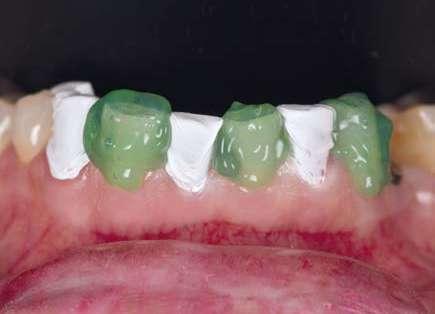

En la arcada superior por el contrario se decidió poner unas carillas de disilicato para poder cubrir las expectativas de la paciente y ajustar el color al que ella deseaba, bajando casi en 5 tonos el color final. Se planificaron preparaciones digitales conservadoras.

La tecnología digital permite lograr el equilibrio de espesores ideal para cada caso, así como un eje de inserción adecuado. Todo esto permite dar una garantía de longevidad a las restauraciones planificadas.

En este caso se realizó una preparación previa a la preparación guiada en los márgenes y zonas interproximales, para camuflar el sustrato y dar una correcta inserción; y posteriormente se utilizaron unas guías de tallado diseñadas digitalmente para obtener los resultados precisos y predecibles que requería el caso.

La preparación previa junto a la preparación guiada, resultaron en un equilibrio ideal para los espesores mínimos que requería el caso. Se realizó una prueba en seco para valorar el ajuste final de las restauraciones.

Para cementar las carillas y evitar movimientos no controlados y una incorrecta cementación, utilizaremos una guía de posicionamiento simultáneo, esta guía no es de cementación en bloque ya que las carillas están perfectamente individualizadas. Únicamente sirven para llevar a la boca del paciente las carillas y cementarlas de una forma 100% segura, evitando el estrés que genera un posible movimiento durante la cementación y acelerando los tiempos de trabajo.